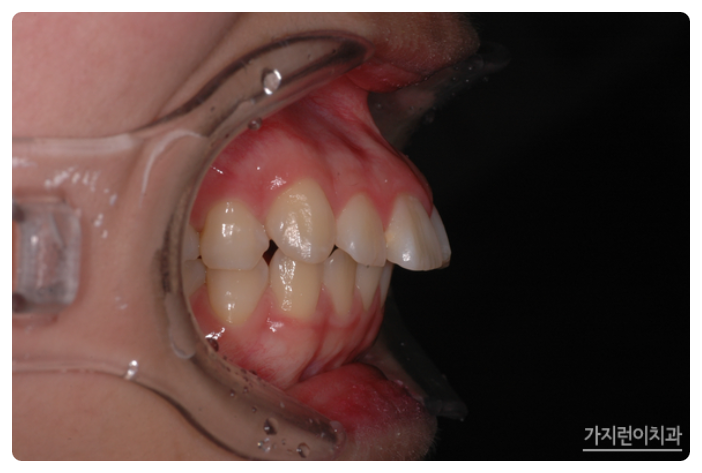

서울가지런이치과교정과 의원을 찾아주신 환자분의 모습인데요. 상악 돌출이 꽤나 심한 것을 볼 수 있습니다. 이런 경우에는 입술을 다무는 것이 어려운 정도였는데요. 전체적으로 치아를 후방으로 이동할 필요가 있어 돌출입 교정과 거미스마일 교정을 진행하게 되었습니다.